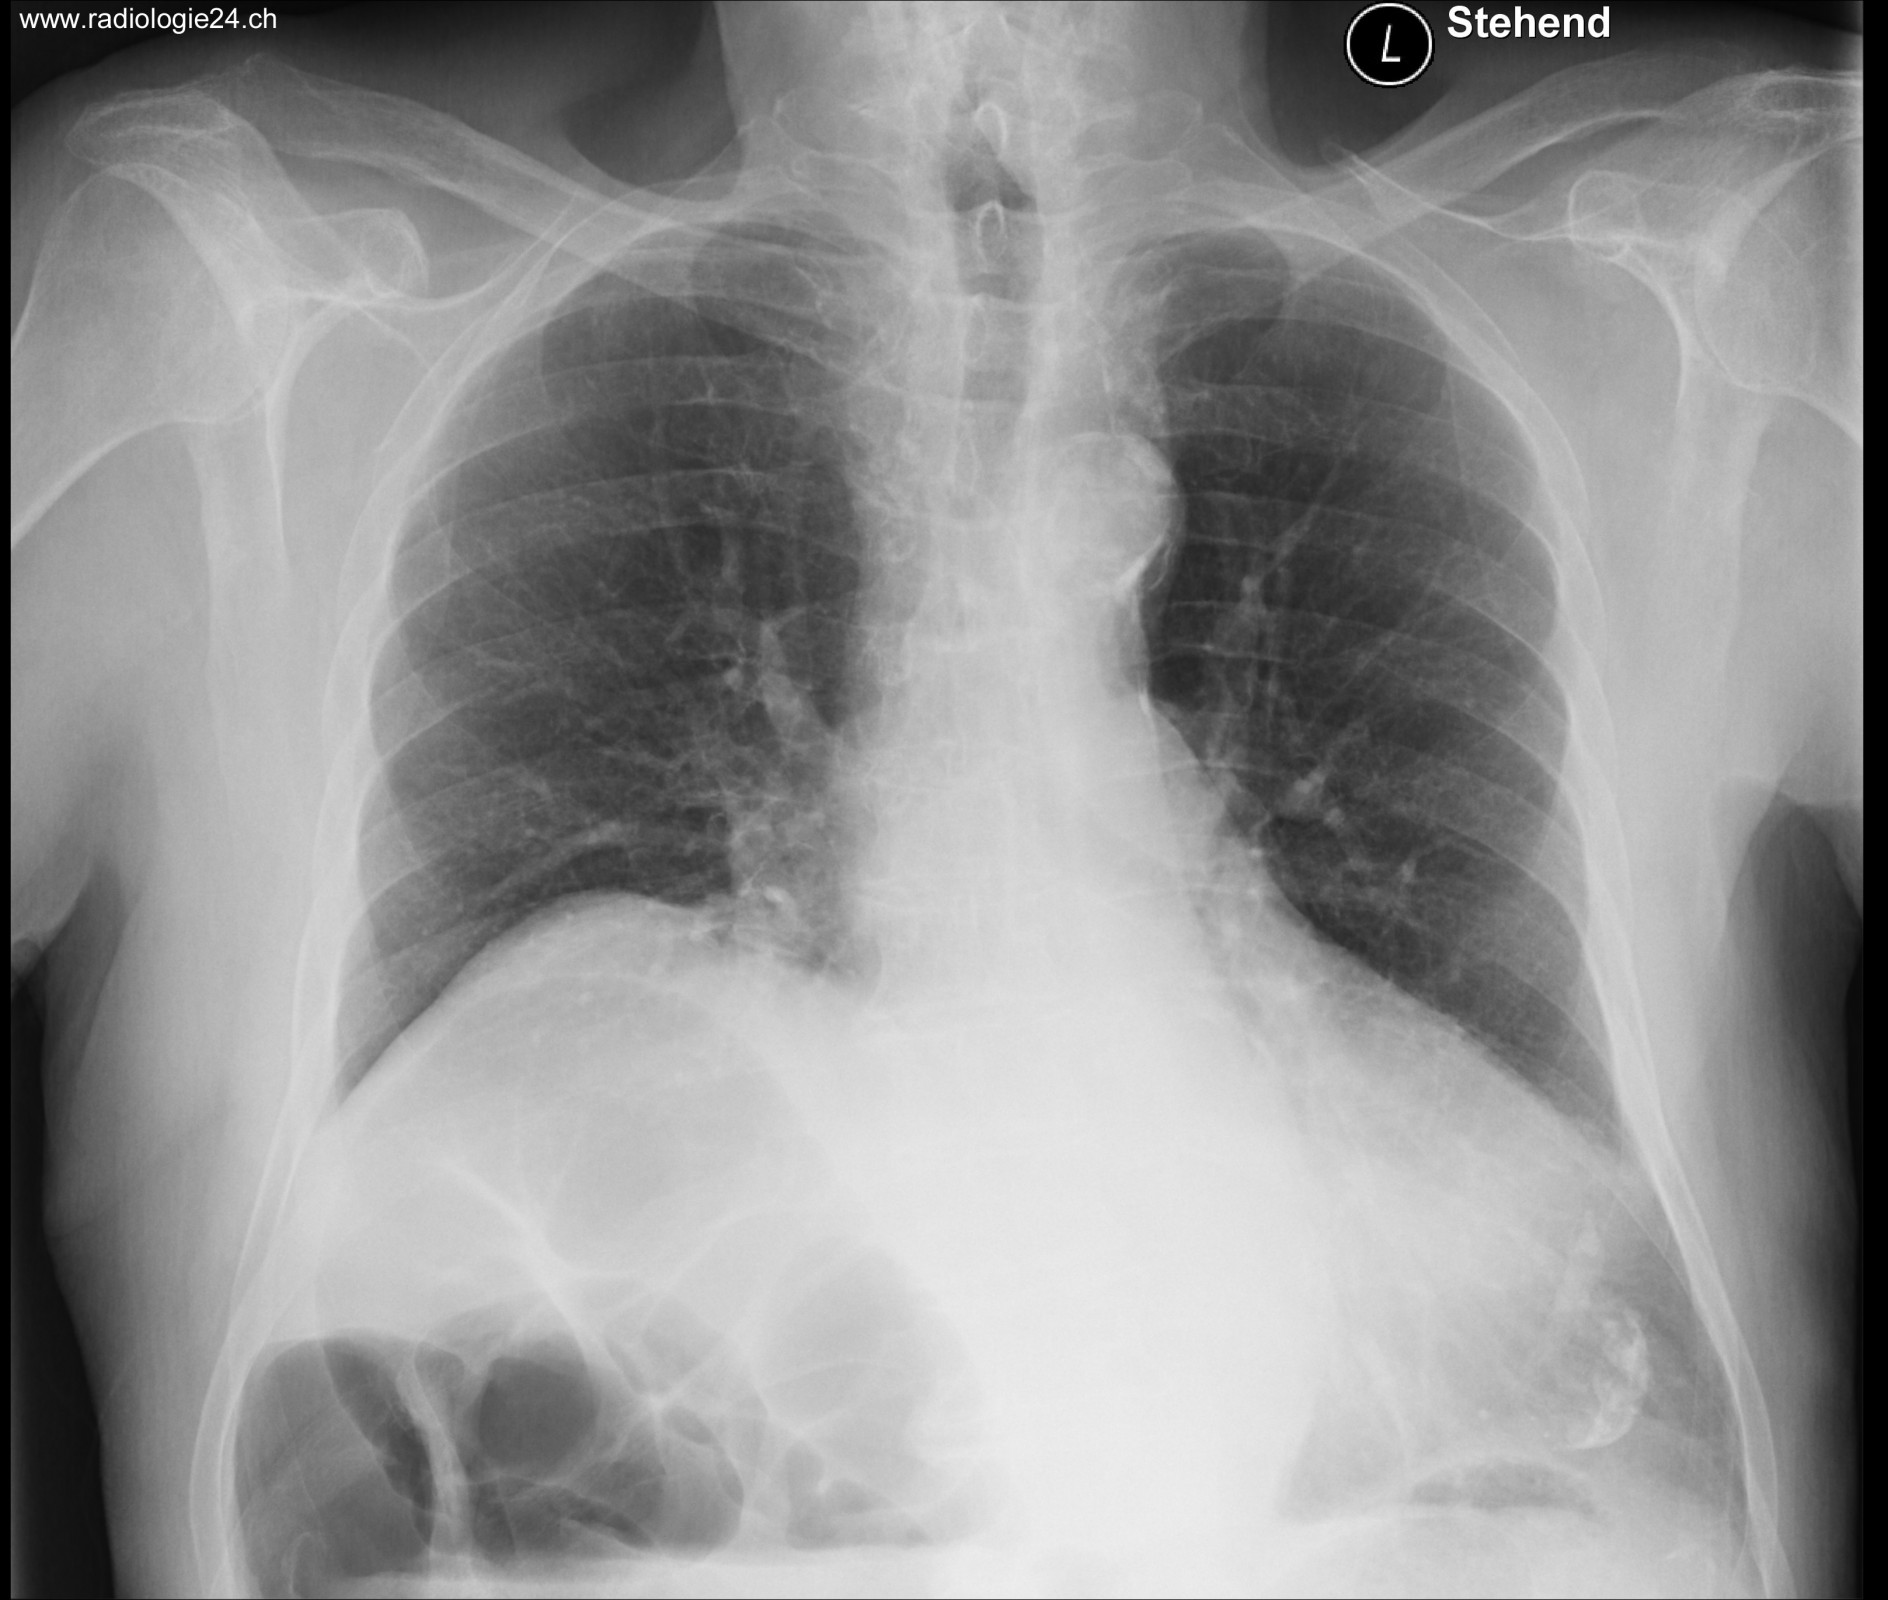

Röntgenfall des Monats Juli 2017 mit Auflösung

78 jähriger Patient mit zunehmender Dyspnoe und Thoraxschmerzen

ap

Bild vergrössern